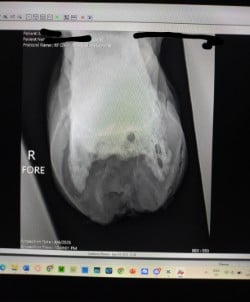

Rennie, a 2016 AQH, is a medical mystery; by all means, he shouldn't be standing, running, or jumping around the paddock. He was rescued in 2023 by a small family who help horses, skin and bones with a severe and constant limp in his right foreleg. We got him in February 2024, a great weight, but he still had a mysterious lameness that we couldn't figure out. After research, I found scoot boots. They took him from constant 3-4/5 lameness to a 1-2 lameness. Sound to be ridden (although he is just a paddock pet) We took x-ray at Texas A&M, the whole team was shocked, wondering how he is still alive with full fusion of his coffin, navicular and P3. His not only walking, but he is sound, happy, and a loving liberty pony. He came from a background of severe abuse. He has the physical and emotional scars of control-based training methods that left deep trauma: rope burns, whip marks, slashed legs, and twisted ears told a story of cruelty I wouldn’t wish on any animal. He had spent his final months before rescue in the auction pipeline.

I turned back to Rennie’s old farrier, the only one he and I trusted, but his flare-ups worsened, and without clear x-rays, we had little understanding of what was truly happening inside his hoof. I consulted my vet about quality of life, corrective shoeing, and every option we had left. When Texas A&M provided new x-rays, the truth was undeniable. His fusion was so severe that most professionals believed there was no choice but euthanasia. One corrective shoer refused to even see him, stating simply, "The horse should be put down."

But the team at Texas A&M saw what I saw—Rennie was defying the odds. Corrective shoeing wasn’t the answer. Traditional shoes would only add more stress, but Scoot Boots gave him freedom. They allowed his hoof to move as naturally as possible, relieving pressure without restricting movement. The specialists were amazed—not just at his ability to move, but at how much the boots had helped him. Without them, he wouldn’t be sound. Without them, I would have had to make the hardest decision.